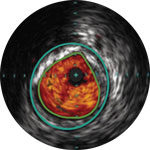

Eine Angiographie liefert Informationen über die luminalen Eigenschaften peripherer Arterien, unterbewertet aber das Ausmass der Atherosklerose bei Patienten mit peripherer arterieller Verschlusskrankheit (pAVK) erheblich, selbst bei „normal erscheinenden“ Gefässen.1

Die IVUS-Technologie von Philips liefert detaillierte Läsionsbilder, die Ihnen die Entscheidung über das optimale Vorgehen erleichtern.

Dr. Stavroulakis erörtert, wie der Schweregrad einer pAVK durch eine reine Angiographie häufig unterschätzt wird und wie mithilfe von IVUS der prozentuale Stenosegrad und die Plaque-Belastung präzise gemessen und quantifiziert werden können.